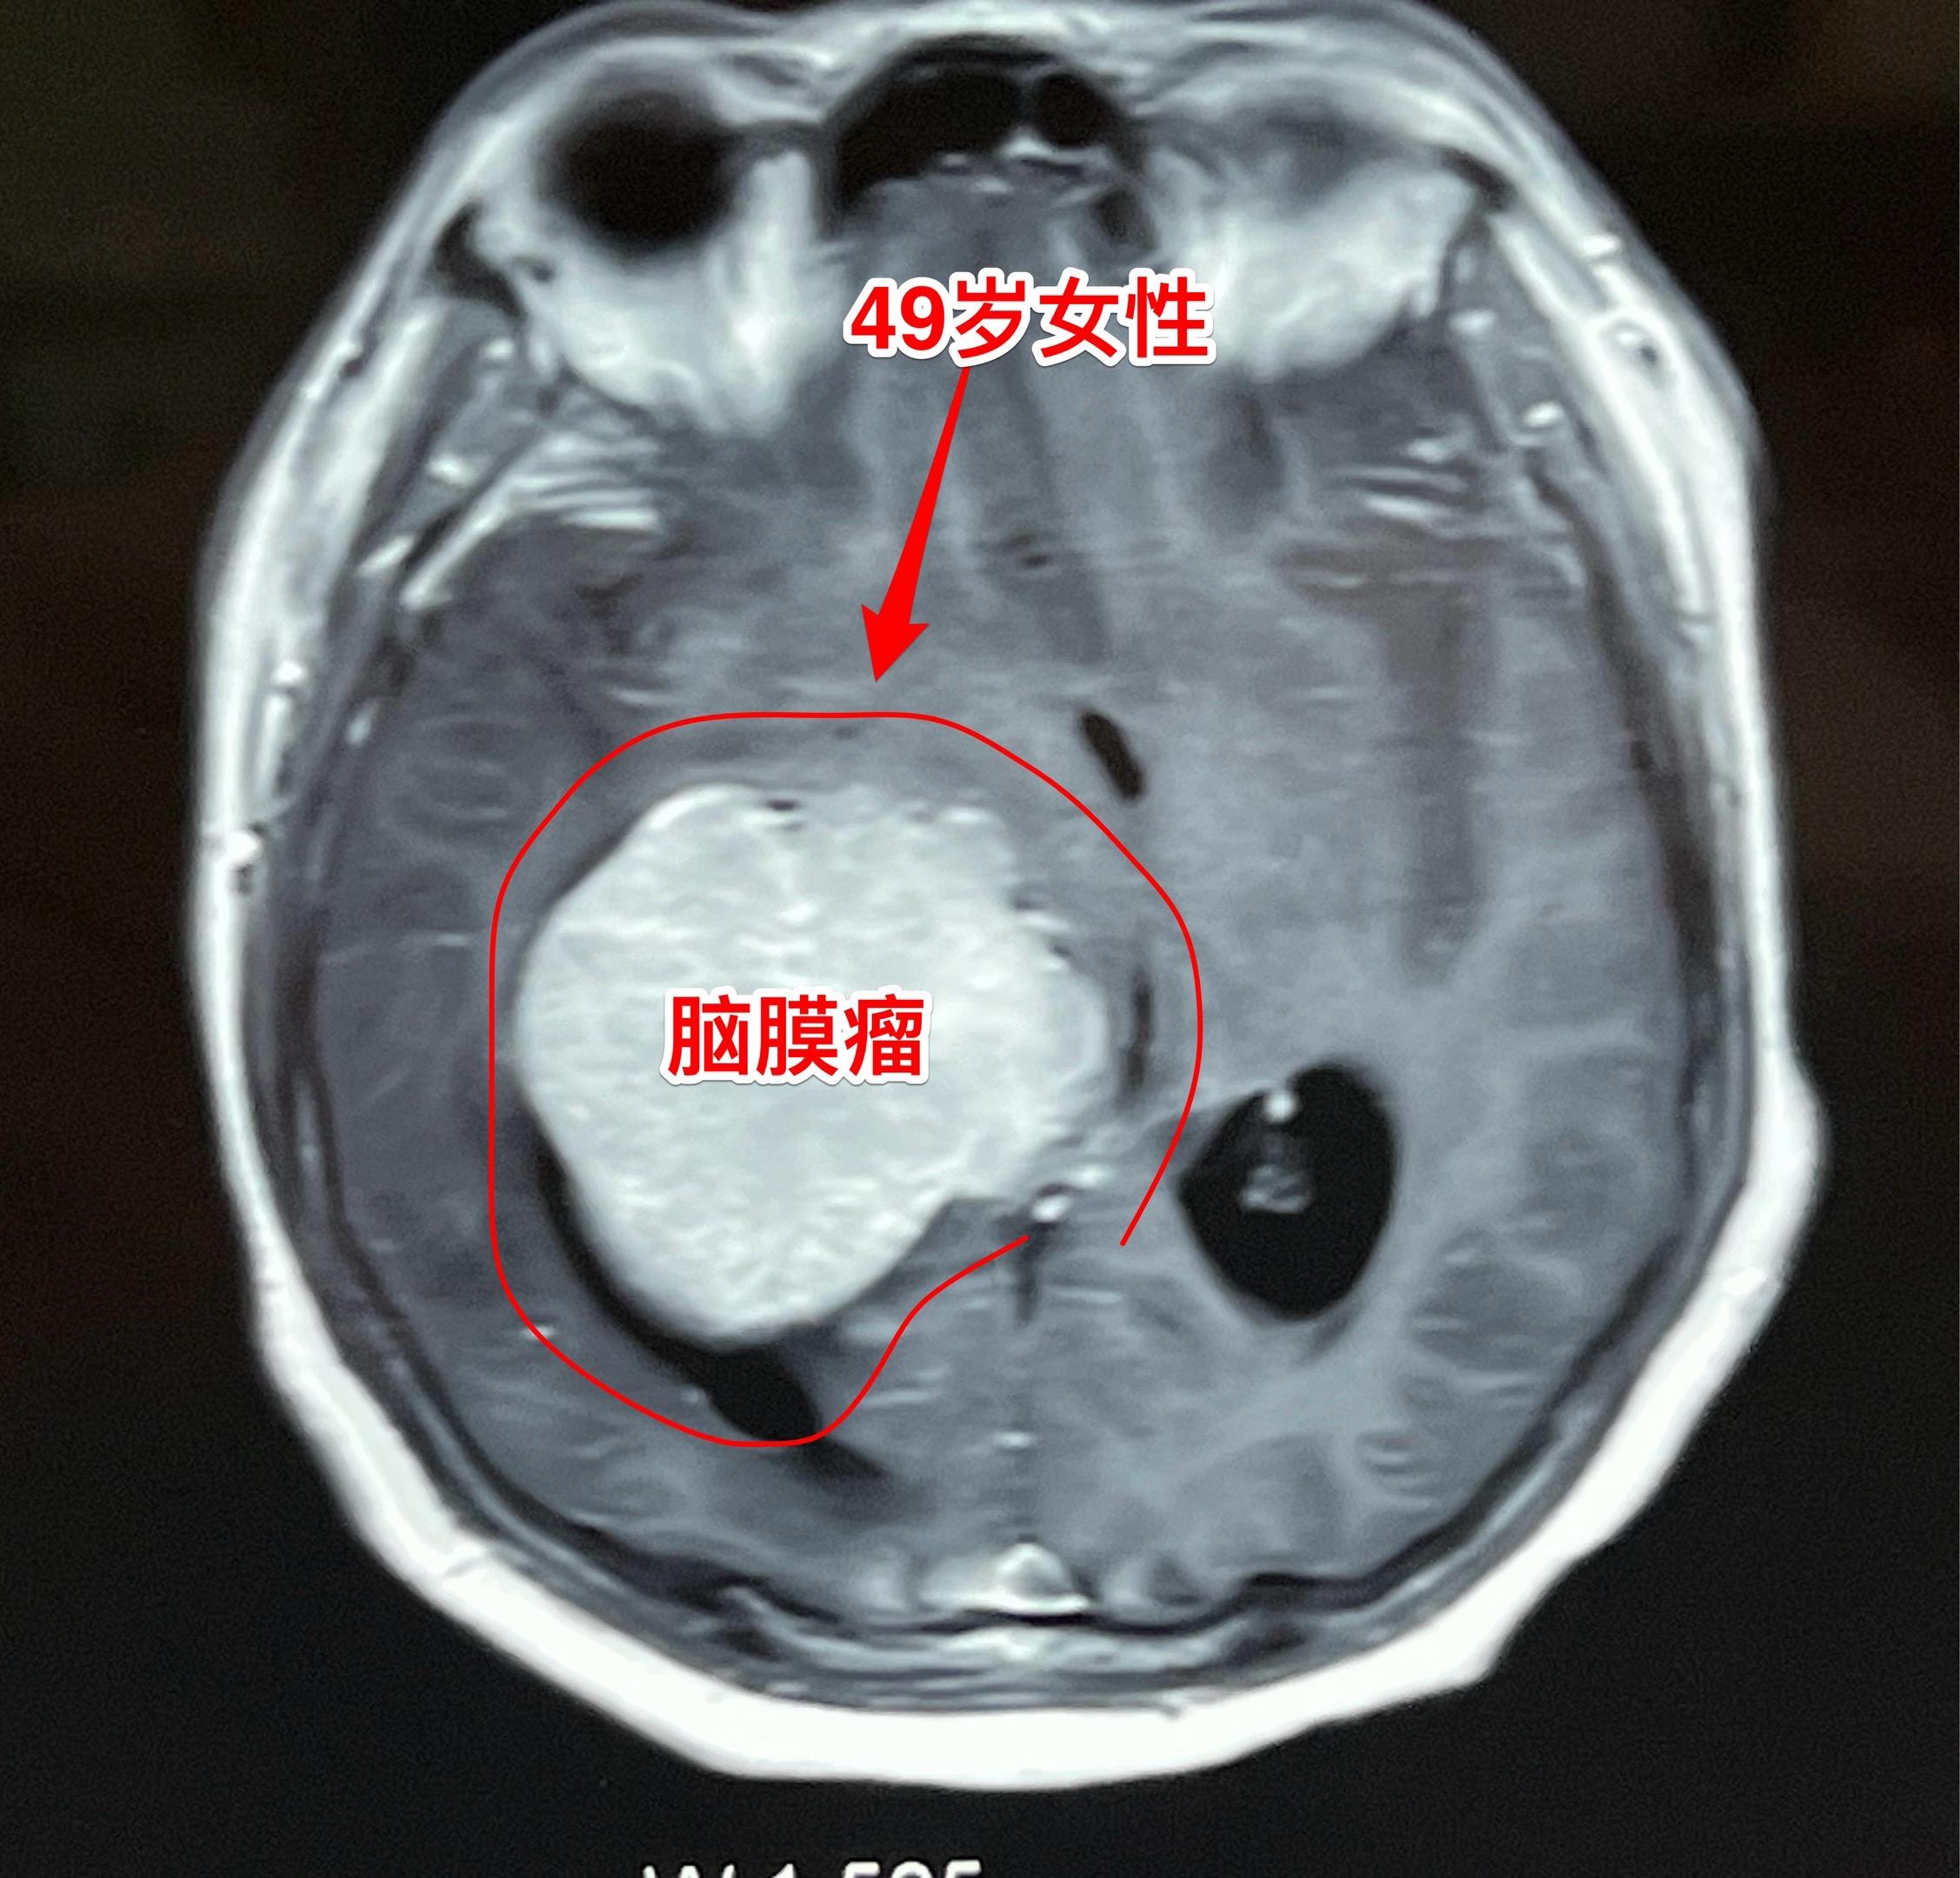

脑室内脑膜瘤也是良性肿瘤。49岁朝鲜族女性,在韩国工作,因头痛、呕吐发现这个肿瘤,随即回国治病。 这个肿瘤位于右侧脑室的三角区,脑室内的脑膜瘤最好发于这个位置。如果作手术彻底切除这个肿瘤,可以获得治愈。